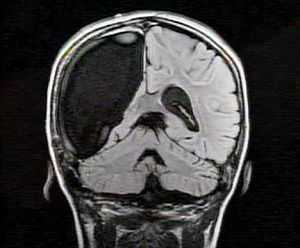

Обследование пациентов включало клиническое изучение семиотики приступов, неврологическое и нейроофтальмологическое обследование, нейропсихологическое тестирование, магнитно-резонансную томографию (МРТ) по программе «эпилепсия», использование нейрофизиологических (инвазивных и неинвазивных методов). Проводилось также гистологическое изучение удаленных при операции эпилептогенных участков головного мозга.

По данным МРТ головного мозга 3,0 Тесла у 28 (45%) пациентов было выявлено эпилептогенное поражение (МР-позитивные формы), у 33 (55%) пациентов видимой патологии выявлено не было (МР-негативные формы).